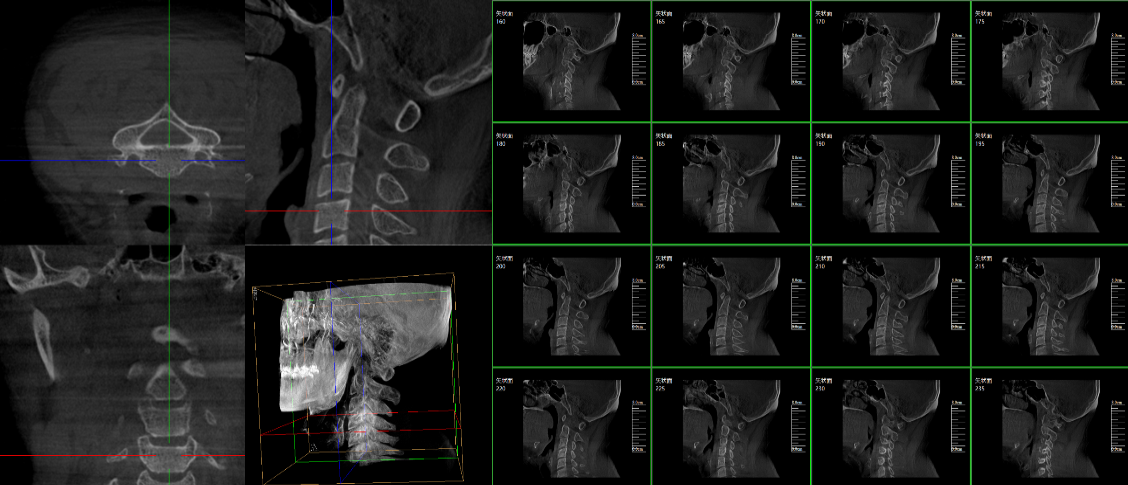

現(xiàn)在很多廠家或者經(jīng)銷商都在推廣三維c型臂,那么,三維c型臂是什么意思?三維c型臂是一款新型C形臂,實(shí)現(xiàn)了術(shù)中影像從二維到三維的飛躍。通過不同方位的斷層圖像,能夠更清晰、完整地顯示椎體及其附件的解剖學(xué)結(jié)果,直觀地分析病變與周圍組織的立體空間關(guān)系,三維斷層成像能夠使手術(shù)模擬和手術(shù)方案的制定更加準(zhǔn)確。

普愛醫(yī)療是專業(yè)生產(chǎn)c型臂廠家,在國內(nèi)率先掌握三維成像技術(shù),繼國內(nèi)首例三維影增c型臂后,又推出國產(chǎn)品牌等中心平板移動(dòng)式三維C形臂X射線機(jī)——天弓PLX7500三維c型臂。該設(shè)備擁有優(yōu)異的術(shù)中三維成像技術(shù);高品質(zhì)數(shù)字化影像鏈;超大三維成像區(qū)域;穩(wěn)定全面的圖像采集;便捷簡易的操作體驗(yàn);全電動(dòng)的運(yùn)動(dòng)控制;低劑量模式;無線導(dǎo)航傳輸;多屏同顯等特點(diǎn)。

脊柱外科的應(yīng)用:有研究表明,在三維c型臂圖像引導(dǎo)的下頸椎或胸椎后路螺釘置入術(shù)中,螺釘正確置入率可達(dá)92.7%,在三維c型臂圖像引導(dǎo)的椎間孔腰椎椎間盤融合術(shù)中,術(shù)者被輻射總量明顯降低。此外三維c型臂可以搭配骨科手術(shù)導(dǎo)航和機(jī)器人使用,能將該過程智能化和準(zhǔn)確化,進(jìn)一步提高螺釘?shù)闹踩肼省?/span>

創(chuàng)傷外科的應(yīng)用:由于創(chuàng)傷外科的患者多數(shù)為急、重癥患者,以致術(shù)前準(zhǔn)備時(shí)間較短,很多都需行急診手術(shù),三維c型臂可以在術(shù)中實(shí)時(shí)重建三維圖像,使手術(shù)醫(yī)生對(duì)一些復(fù)雜骨折更加充分的了解,并且能夠在術(shù)中即時(shí)校正螺釘?shù)奈恢?,更加精確地置入固定器材,減少術(shù)中及術(shù)后發(fā)生并發(fā)癥的幾率,極大限度地縮短螺釘置入時(shí)間。